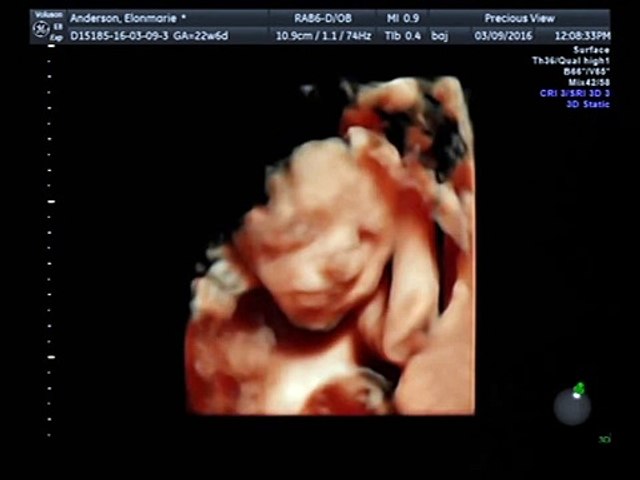

3d Pregnant Video